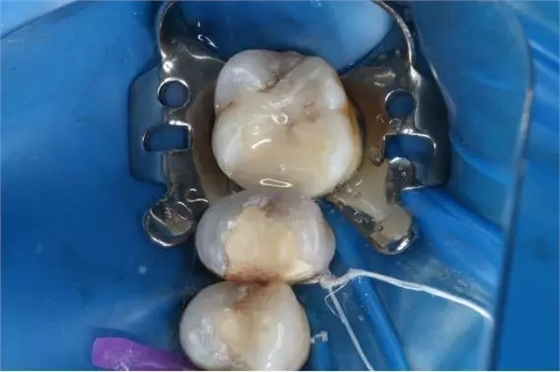

12.完美出爐

640.webp (11).jpg

13.上橡皮障戴牙

640.webp (12).jpg

14.酸蝕

640.webp (13).jpg

15.粘結(jié)